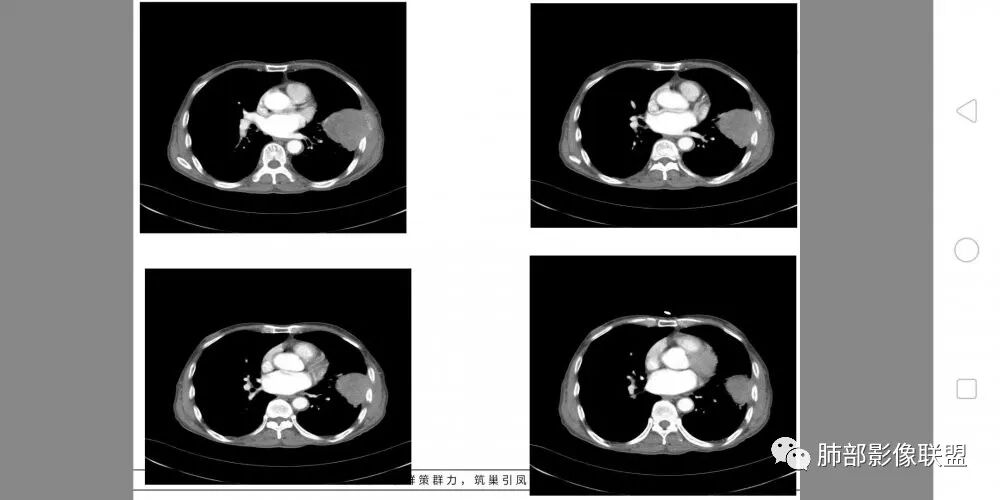

老年男性,外伤入院,“左上肺”实性肿块,边缘光滑,突破壁层胸膜并侵犯肋骨及肋间肌,增强扫描轻度强化,可见明显坏死。

左肺上叶实性肿物,左肺上叶支气管受压变窄,病灶边缘光滑,轻度分叶,病灶轻度强化内部可见多发小灶坏死,坏死边界模糊,病灶突破壁层胸膜侵及左侧部分肋骨及肋间肌,考虑恶性,肉瘤样癌,鉴别诊断低分化腺癌。

左肺上叶胸膜下起源巨大肿块,边缘略有分叶,周围肺组织及支气管推移受压,侵犯胸壁,肋骨破坏,密度不均,其内坏死范围比较大,坏死区边缘清晰,考虑肉瘤样癌。

胸部CT所见左肺上叶尖后段胸膜下较大山丘形肿块,边界清楚,宽基底与胸膜相贴,边缘与胸膜呈直角及锐角相交。邻近上叶尖后段支气管受压推挤,叶裂局部膨隆,病灶周围见少许磨玻璃密度影,边界不清。纵膈窗显示,肿块密度均匀,增强扫描呈不均匀轻度强化,邻近肋骨骨质破坏,病变沿肋间隙向外侵犯,局部胸膜增厚。纵膈内见多发小淋巴结,未见胸腔积液征象。综合考虑恶性占位,肉瘤样癌可能性大。腰椎及髋部考虑骨转移。

毛勤香 广西柳州龙潭医院影像

老年男性,左肺上叶舌段胸膜下肿块,外朝内生长,对应支气管受压变窄,肿块边界清晰,邻近胸膜胸壁和肋骨受侵犯,增强扫描明显不均匀强化,内有较多坏死,考虑恶性,首先肉瘤样癌,鉴别低分化腺癌。

老年男性,病史无特殊。影像:左肺上叶大肿块,宽基底,边界光滑,周围气管血管有推移,略有分叶,明显栽赃,肋骨破坏,恶性肯定没问题,考虑:1.胸膜有掀起,符合肺外的恶性肿瘤,优先考虑。2.左肺上叶尖后段不确定是否阻塞,如果阻塞,考虑肺内,肉瘤样癌,待排。